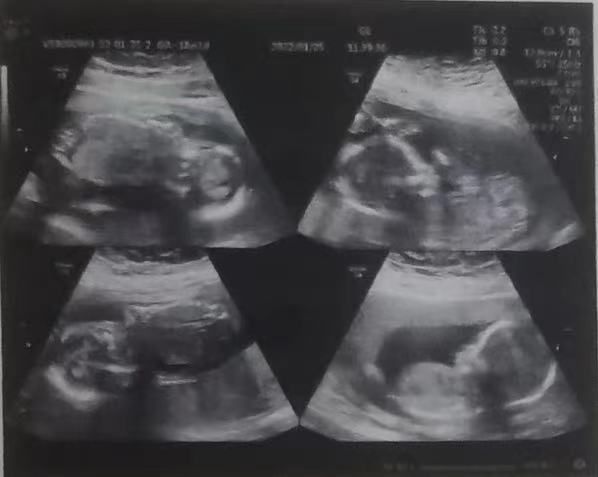

▲檢查畫面。(圖/海報新聞)

據《海報新聞》報導,山東濟寧一名22歲女子第一次當媽媽就懷上四胞胎,遇到非常高的挑戰。3月22日當天,第一胎僅有25週6天就出生了,體重735克,屬於極早早產兒;4天後老二出生,重870克;第三第四胎4月1日出生,分別重1050克和1030克,四胎都是男孩。